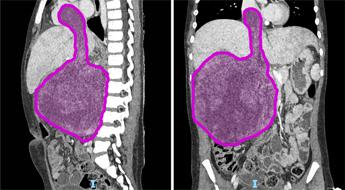

(Adnkronos) – Sei cicli di chemioterapia, poi nove ore di intervento ma ora il tumore di circa 1,5 chili di cui era affetta Sara (nome di fantasia), a soli otto anni, è stato rimosso. "Un intervento chirurgico complesso e straordinario", ha spiegato in una nota l'ospedale pediatrico Bambino Gesù di Roma dove è stata operata la bambina. "Questo successo non è solo una vittoria medica, ma anche una grande speranza per tante famiglie che affrontano situazioni simili", ha affermato Alessandro Crocoli, responsabile dell’Unità di Chirurgia Oncologica. "Sara (nome di fantasia), 8 anni appena compiuti, era affetta da un nefroblastoma al rene destro che si estendeva all’interno della vena renale, della vena cava inferiore fino a raggiungere l’atrio destro del cuore, a causa di una trombosi neoplastica. Questa rara estensione del tumore – ha spiegato l'ospedale – si verifica in appena il 4-10% dei casi di nefroblastoma. Prima dell’intervento Sara è stata sottoposta a sei cicli di chemioterapia, eseguiti dal team di oncologi guidati dal professor Franco Locatelli, per ridurre la massa tumorale e facilitare l’operazione. La fase preparatoria pre-chirurgica si è avvalsa di tecniche all’avanguardia di diagnostica per immagini come l’elaborazione 3D del tumore da asportare realizzata dall’unità di Imaging avanzato cardiotoracovascolare e fetale". "L’intervento, reso possibile dalla collaborazione tra oncologi, chirurghi, cardiochirurghi, e anestesisti, rappresenta un risultato importante per la medicina pediatrica", ha reso noto l'ospedale pediatrico Bambino Gesù. L’operazione ha avuto una prima fase in cui l’équipe di chirurgia oncologica, formata dal dottor Alessandro Crocoli e dalla dottoressa Chiara Grimaldi, ha rimosso il rene destro, "il cui volume era dieci volte superiore rispetto alla norma a causa del tumore. Successivamente i cardiochirurghi, guidati dal professor Lorenzo Galletti e con il dottor Gianluca Brancaccio come primo operatore, hanno temporaneamente arrestato il cuore della bambina, mantenendola in vita con la circolazione extracorporea, per rimuovere la parte del tumore che aveva invaso l’atrio destro – prosegue la nota dell'ospedale del Vaticano – Infine, dopo aver riavviato il cuore, i chirurghi hanno completato l’operazione rimuovendo il residuo tumorale dalla vena cava inferiore. In totale, il tumore asportato pesava circa 1,5 kg. La parte anestesiologica del complesso intervento, durato più di 9 ore, è stata gestita dal team della Terapia Intensiva Cardiochirurgica del dottor Luca Di Chiara". "Questo successo non è solo una vittoria medica, ma anche una grande speranza per tante famiglie che affrontano situazioni simili: rappresenta un traguardo straordinario nella chirurgia oncologica pediatrica. Rimuovere un tumore di queste dimensioni, così invasivo, è stato possibile solo grazie a una pianificazione chirurgica estremamente accurata e alla collaborazione di un’équipe multidisciplinare altamente specializzata – ha detto Alessandro Crocoli, responsabile di Chirurgia Oncologica – La priorità è stata garantire il miglior risultato possibile, con un approccio personalizzato e sicuro". "L’asportazione della massa tumorale che invadeva il cuore ha richiesto l’arresto cardiaco e l’uso della circolazione extracorporea, procedure complesse che esigono il massimo coordinamento – ha commentato il professor Lorenzo Galletti, responsabile di Cardiochirurgia – Questo intervento dimostra come, unendo competenze avanzate e tecnologia d’avanguardia, possiamo affrontare anche i casi più difficili, restituendo speranza ai nostri giovani pazienti". Dopo una breve degenza in terapia intensiva, Sara "sta proseguendo la convalescenza in modo positivo e riceve le cure necessarie per un recupero ottimale. La scorsa settimana ha festeggiato il suo ottavo compleanno in reparto con la famiglia e con i medici che si stanno prendendo cura di lei. Il suo percorso di cura continuerà con sedute di radioterapia addominale e ulteriori cicli di chemioterapia", conclude l'ospedale. Il nefroblastoma, noto anche come tumore di Wilms, "è una neoplasia rara che colpisce prevalentemente i bambini tra 1 e 5 anni, con un picco tra i 2 e i 3 anni. Rappresenta circa il 90% dei tumori renali pediatrici, anche se i tumori al rene costituiscono meno del 5% delle neoplasie in età pediatrica – ricorda l'ospedale – In Italia, la sua incidenza è di circa 8 casi ogni milione di bambini. I reni si formano durante lo sviluppo embrionale a partire da alcune particolari cellule staminali dette progenitrici. In alcuni casi, queste cellule persistono nei reni dopo la nascita e, a causa di mutazioni genetiche, possono proliferare in modo incontrollato, portando alla formazione del nefroblastoma". —cronacawebinfo@adnkronos.com (Web Info)